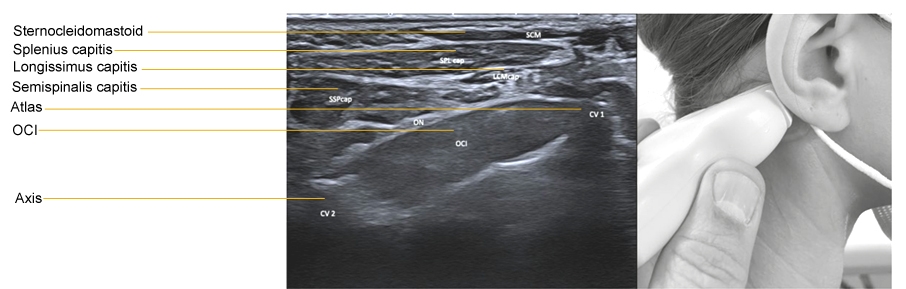

1. Place the convex transducer horizontally on the posterolateral neck at a level just below the tip of the mastoid process.

2. Rotate the dorsal end of the transducer a little downward, and turn the transducer a little in a rostral direction.

3. Identify the OCI. Normally, it is sausageâ€like, but may become ovoid in shape when it is hyperactive. The vertebral artery is just beneath the muscle. Confirm it with the color Doppler imaging. When the OCI is difficult to detect, because of intramuscular fibrosis the vertebral artery may help identify the muscle. There are occasionally other arteries superficial to the OCI.

4. Measure the approximate depth from the skin to the OCI and the muscle thickness before needle insertion in order to penetrate the muscle and not injure the vertebral artery.